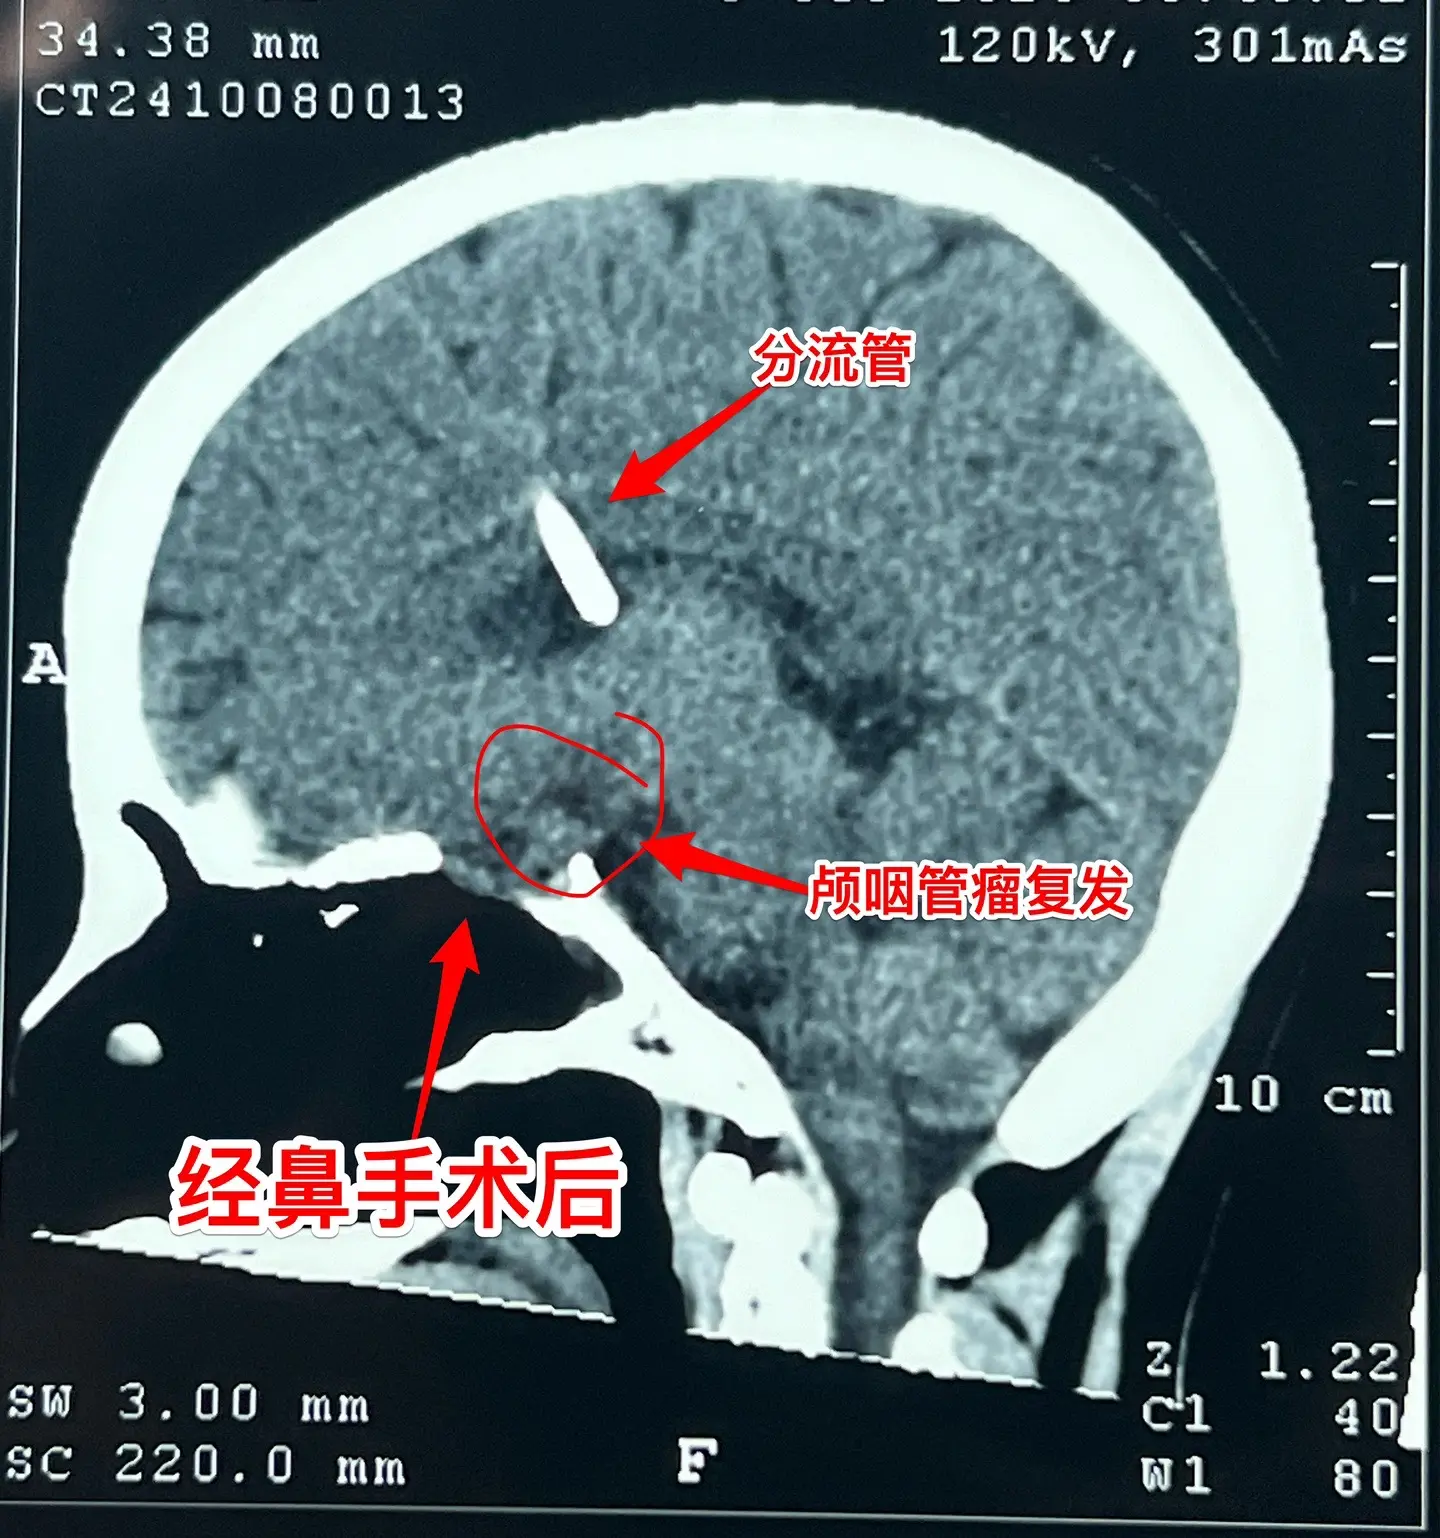

一天完成两个颅咽管瘤手术几乎成了常态。今天的两个颅咽管瘤手术,强度很大哦! 1,4岁男孩子,视力下降。典型的造釉细胞型颅咽管瘤,属于鞍隔下颅咽管瘤。开颅手术将颅咽管瘤完全切除,垂体大部分保留,垂体柄保留,下丘脑保护完好。这样的结果我们很满意! 2,35岁女性,经鼻手术后颅咽管瘤复发,视力下降。是乳头型颅咽管瘤。肿瘤与视交叉粘连很紧,手术分离难度大,最终得到完全切除。